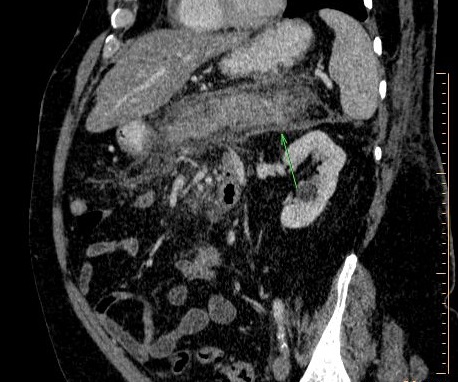

Affection oedemateuse peut

s'etendre au dela du pancreas et se densification de

la graisse peri-pancreatique ( fleche rouge ) .

Image radiologique TDM en coupe sagitale |

Affection inflamatoire du pancreatite

peut s'etendre et affecte d'epaissisement de la

facia pararenal ( fleche rouge ) . Image radiolgique

TDM encoupe axiale phase arteriel |